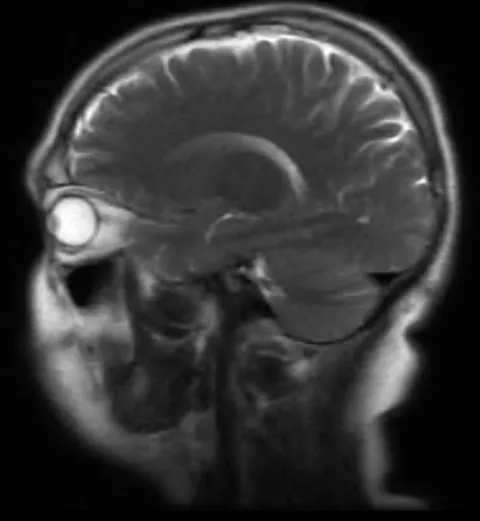

So I had an MRI last week and, kinda scary. So I had an MRI last week and, kinda scary.

So I had an MRI last week and, kinda scary.